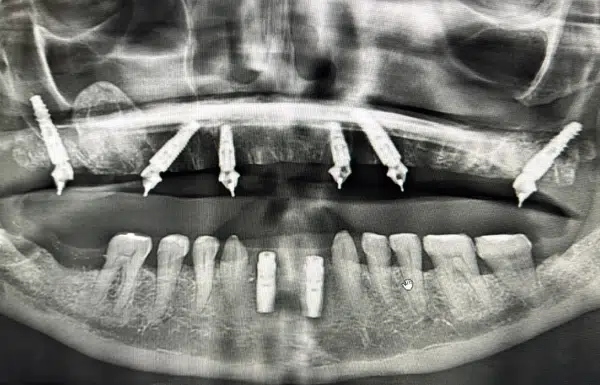

upper fixed arch zirc

Before